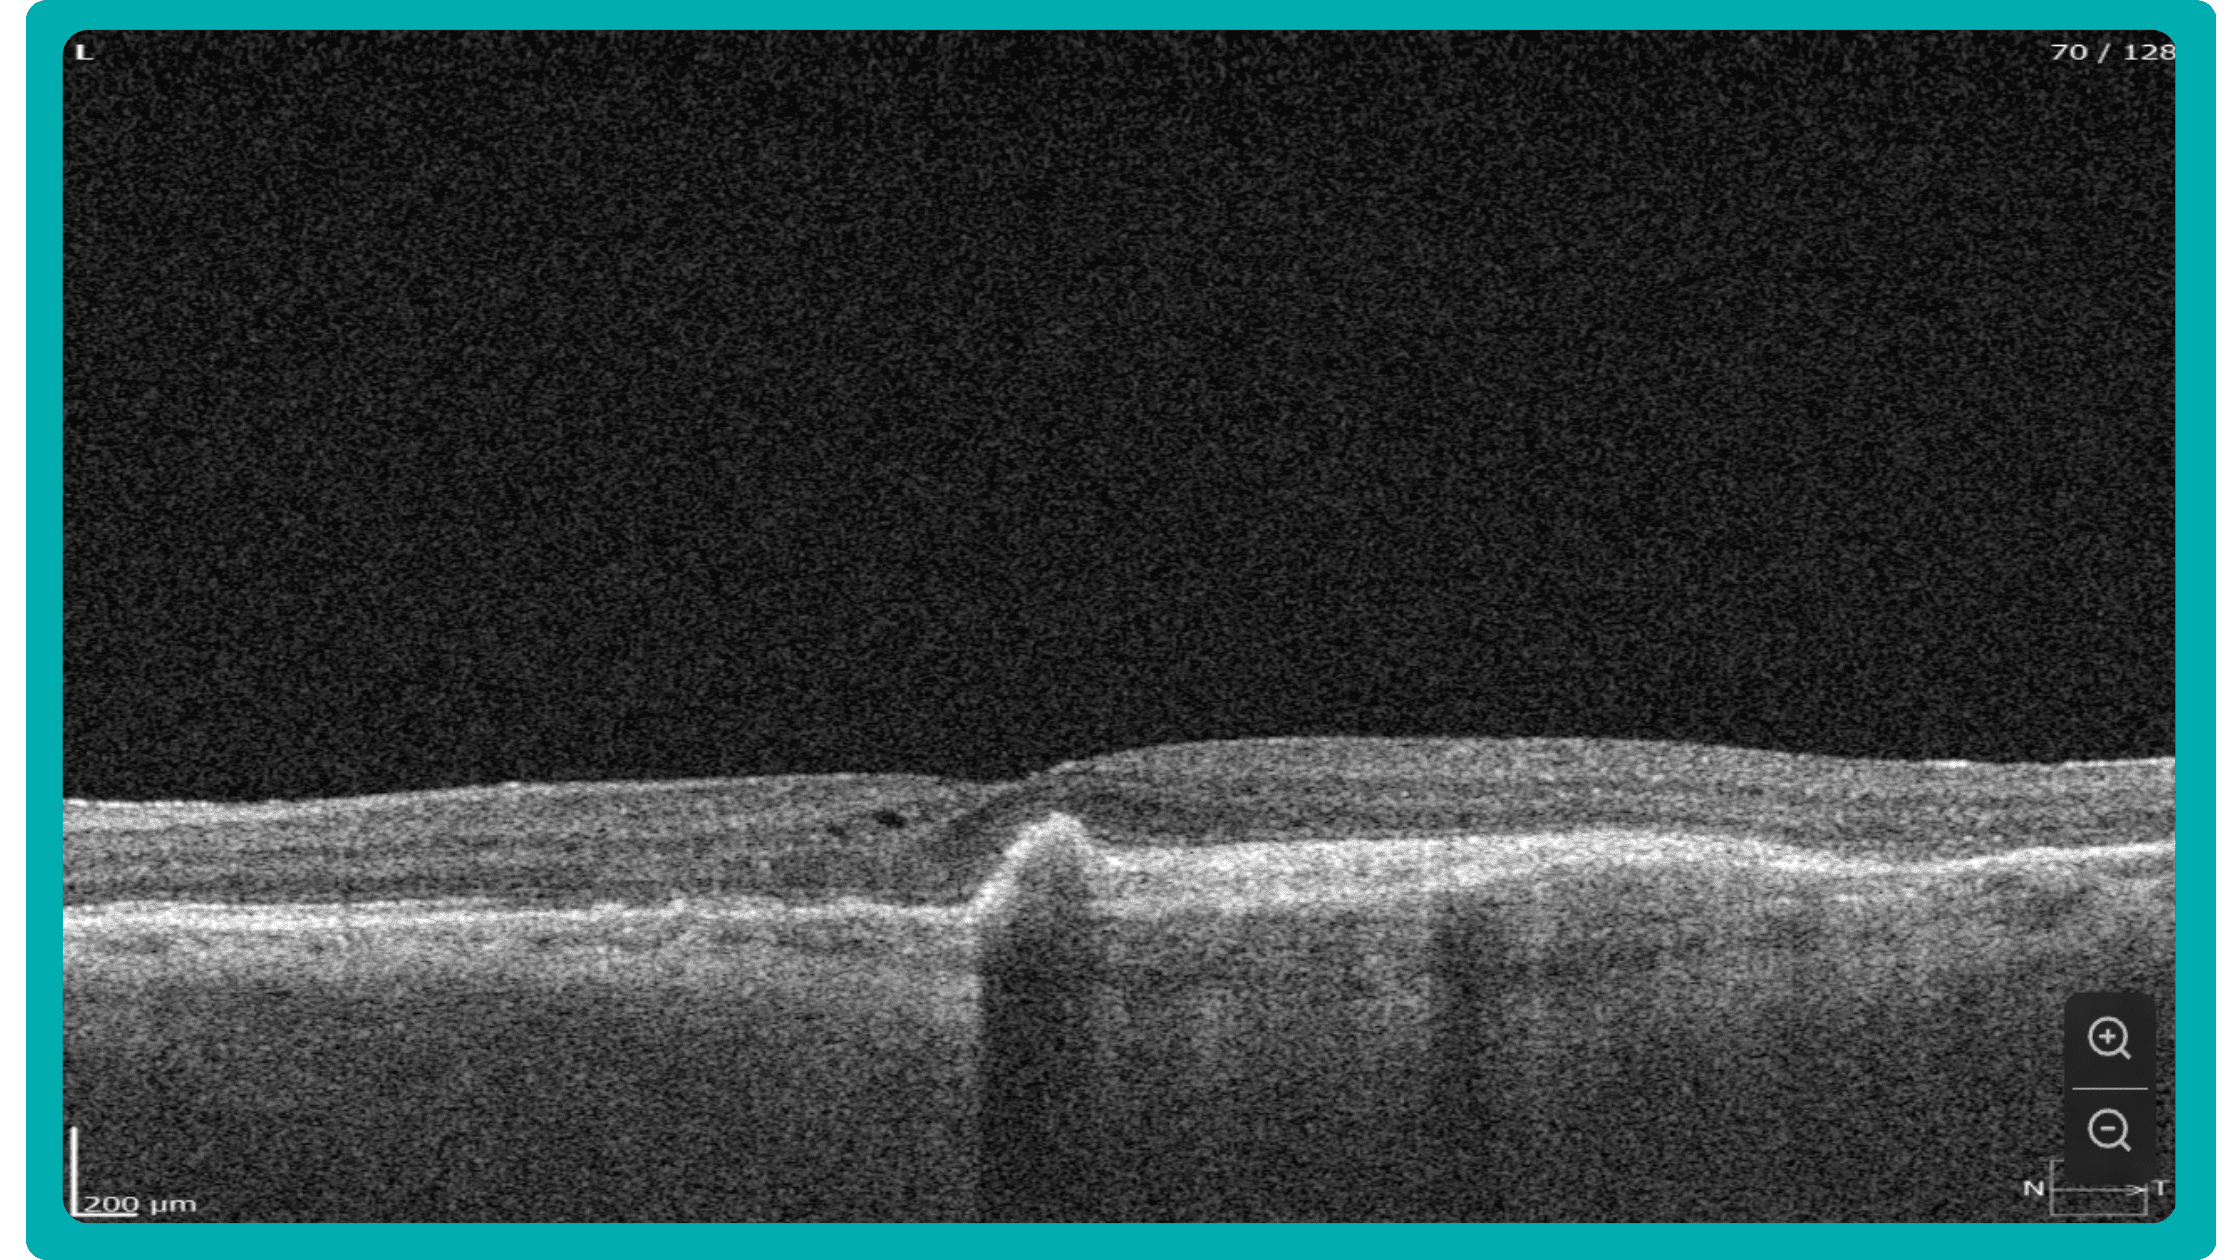

Dr. Maria Sampalis, OD, the owner of Sampalis Eye Care, Rhode Island, utilizes two such programs in her practice. To support her specialization in dry eye management, she employs CSI Dry Eye. Additionally, she uses Altris AI, an AI-powered platform for OCT scan analysis, to provide a second opinion and enhance diagnostic accuracy.

Dr. Sampalis finds that the Dry Eye software allows her and her staff to analyze symptoms and images comprehensively, improving patient care, time savings, and increasing diagnostic precision. See how OCT AI works here.

Her patients also appreciate Altris AI, which analyzes OCT scans for over 70 pathologies and biomarkers while also calculating the risk of developing glaucoma.

Working with specialized software solutions improves diagnostic accuracy and aids in patient education. Visual representations of their conditions, facilitated by these technologies, empower patients with a clearer understanding, leading to increased treatment compliance.

Eye Place, an optometry center in Columbia, also leverages Altris AI, among other cutting-edge technologies. They capture images using the Topcon Maestro2 OCT and use Image Net6 software to export DICOM files to the Altris AI platform.